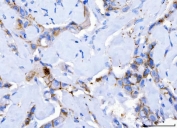

Desmoglein 2 Antibody Breast Cancer IHC. Immunohistochemistry analysis of FFPE human breast cancer tissue stained with DSG2 antibody detecting Desmoglein 2. Tumor epithelial cells show membranous and cytoplasmic staining with focal accentuation at cell-cell borders, consistent with DSG2 localization in desmosomal adhesion complexes that maintain epithelial cohesion. Surrounding stromal elements display minimal staining. Hematoxylin counterstain highlights nuclei in blue. HIER: boil tissue sections in pH 8 EDTA for 20 min and allow to cool before testing.